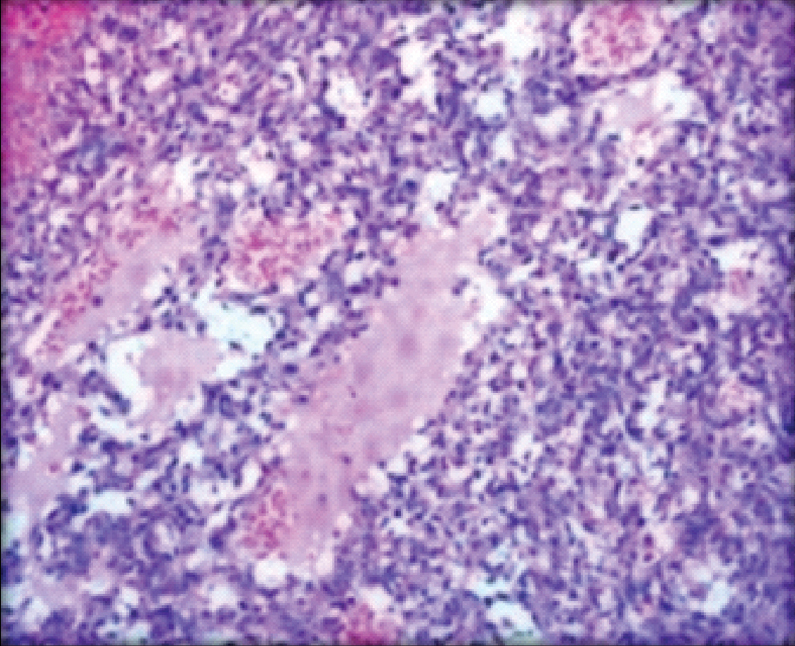

We received a simple mastectomy specimen which measured (13.0x8.0x5.0) cm. Cut surface showed a well circumscribed tumour with areas of haemorrhage measuring (7.5x7.0x5.0) cm. The tumour was 1.5 cm away from the deep resected margin [Table/Fig-2]. On microscopy, sections from the tumour showed anastomosing irregular vascular channels that were dissecting the stroma and were filled with RBC’s. The spaces were lined by epithelioid cells. The cells showed neo lumina formation [Table/Fig-3]. Sheets of tumour cells with high mitotic activity were observed at places. Areas of haemorrhage and ischaemic necrosis were noted [Table/Fig-4]. The nipple areola and deep resected margin were free of tumour. A diagnosis of angiosarcoma was given which was confirmed by Immunohistochemistry (IHC) (CD 34 and factor VIII) [Table/Fig-5].

Areas of necrosis and haemorrhage (H&E, 10X).